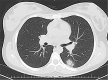

Results: A total of 39 studies with 850 pediatric patients were reviewed. 225 (26.5%) of patients had normal CT findings. Ground-glass opacities and consolidations were the most common CT abnormalities (384/625, 61.5%). Other findings were halo sign, interstitial opacities, bronchial wall thickening, and crazy-paving sign. Approximately 55% of patients had unilateral pulmonary findings. Most studies found peripheral and lower-lobe distribution to be a prominent imaging finding.

Conclusion: Our study showed that imaging findings in children were often milder and more focal than adults, typically as ground-glass opacities and consolidations with unilateral lower-lobe predominance, which have been regressed during the recovery time. A balance must be struck between the risk of radiation and the need for chest CT. If still necessary, low-dose CT is more appropriate in this age group. Albeit, due to the limited number of reported pediatrics with COVID-19, and the lack of consistency in CT descriptors, further work is still needed in this regard.